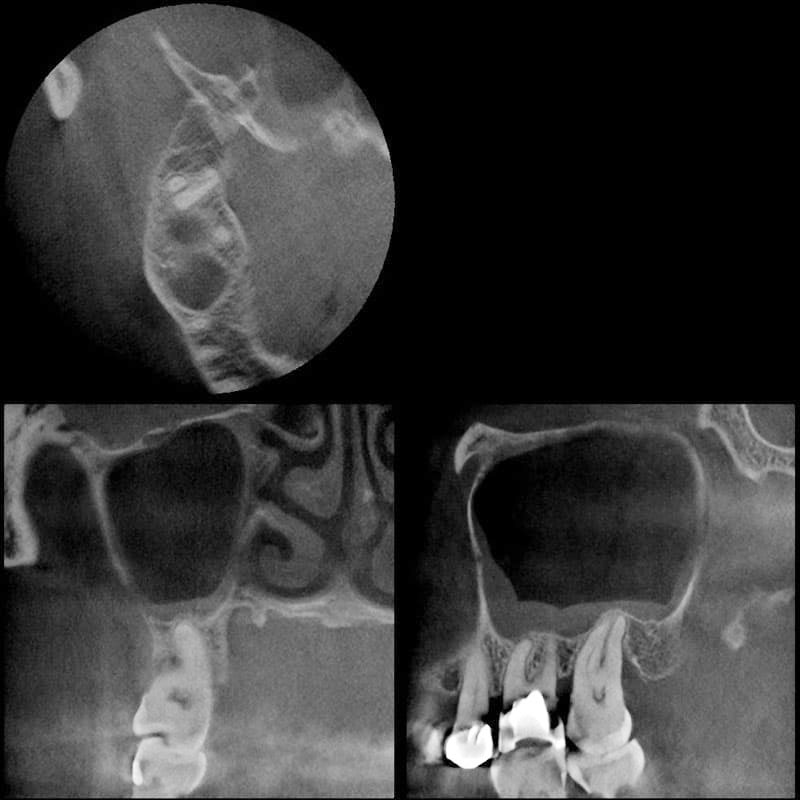

Ihre Praxis für die digitale Volumentomographie (DVT)